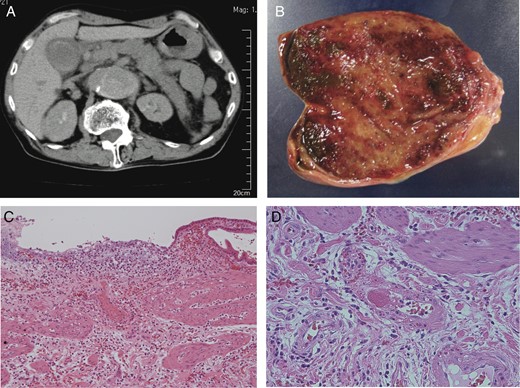

A 74-year-old male who complained of acute back pain was admitted to the hospital. He was diagnosed with Stanford type B aortic dissection and immediately underwent conservative treatment. On 65th hospital day, he suddenly developed high fever and severe right hypochondrial pain with local muscular defense, but laboratory data were within normal range. In the sonographic study, the gallbladder wall was not thickened, and neither gallstones nor biliary sludge was detected. However, contrast-enhanced CT demonstrated acalculous cholecystitis with the partial defect of the gallbladder fundus wall. Small fluid collection was found around the deficit (Fig. 2A). Laparotomy showed the perforation of the gallbladder fundus (Fig. 2B). Although no gallstone was found in the resected specimen, histopathological study revealed fibrosis and hemosiderosis in the subserosal layer (Fig. 2C and D). Intimal fibrotic change of arterioles was dominant at the peripheral part of the gallbladder. There was no pathological finding of vasculitis.

(A) CT showed Stanford type B aortic dissection, the wall defect of gallbladder fundus and the local fluid collection. (B) Laparotomy showed the perforation of the gallbladder fundus. (C) Histological examination showed fibrosis and hemosiderosis in the subserosal layer (H&E ×100). (D) Fibrotic change of arterioles was dominant at the peripheral part of the gallbladder (H&E ×100).